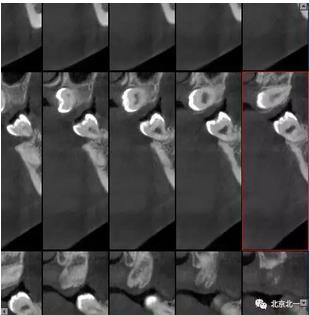

圖四:冠狀面截圖牙根位于唇側(cè),牙冠位于腭側(cè)。

圖五:矢狀位截圖可見(jiàn)牙冠截面。